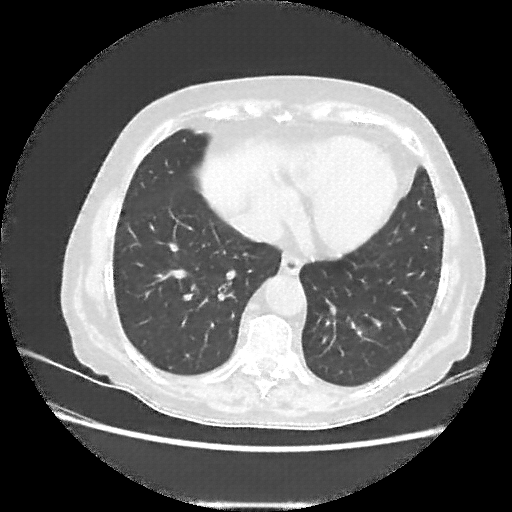

Original VENOUS CT scan

Full window (WL 1023.5, WW 4095 β†’ Low βˆ’1024, High +3071)

Lung window (WL -600, WW 1500 β†’ Low βˆ’1350, High +150)